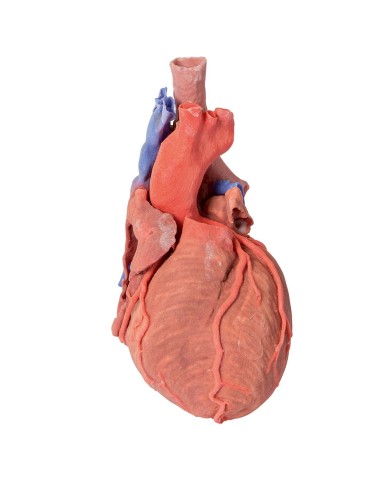

I modellini anatomici di cuore umano sono strumenti indispensabili per uno studio corretto dell'anatomia del cuore umano.

Su Tuttoanatomia trovi la più ampia selezione di prodotti esistente sul web, che va dai cuori normali ai cuori affetti da patologie, per aiutarti a comprendere come le patologie cardiache influiscono e modificano la struttura anatomica cardiaca.

Per una migliore comprensione delle strutture anatomiche del cuore sono stati realizzati anche dei modelli anatomici di cuore ingrandito, si va dai piccoli ingrandimenti fino ai modelli di cuore per la formazione in aula, come il modello anatomico di cuore gigante prodotto da 3B Scientific: un modello di cuore ingrandito di ben otto volte.